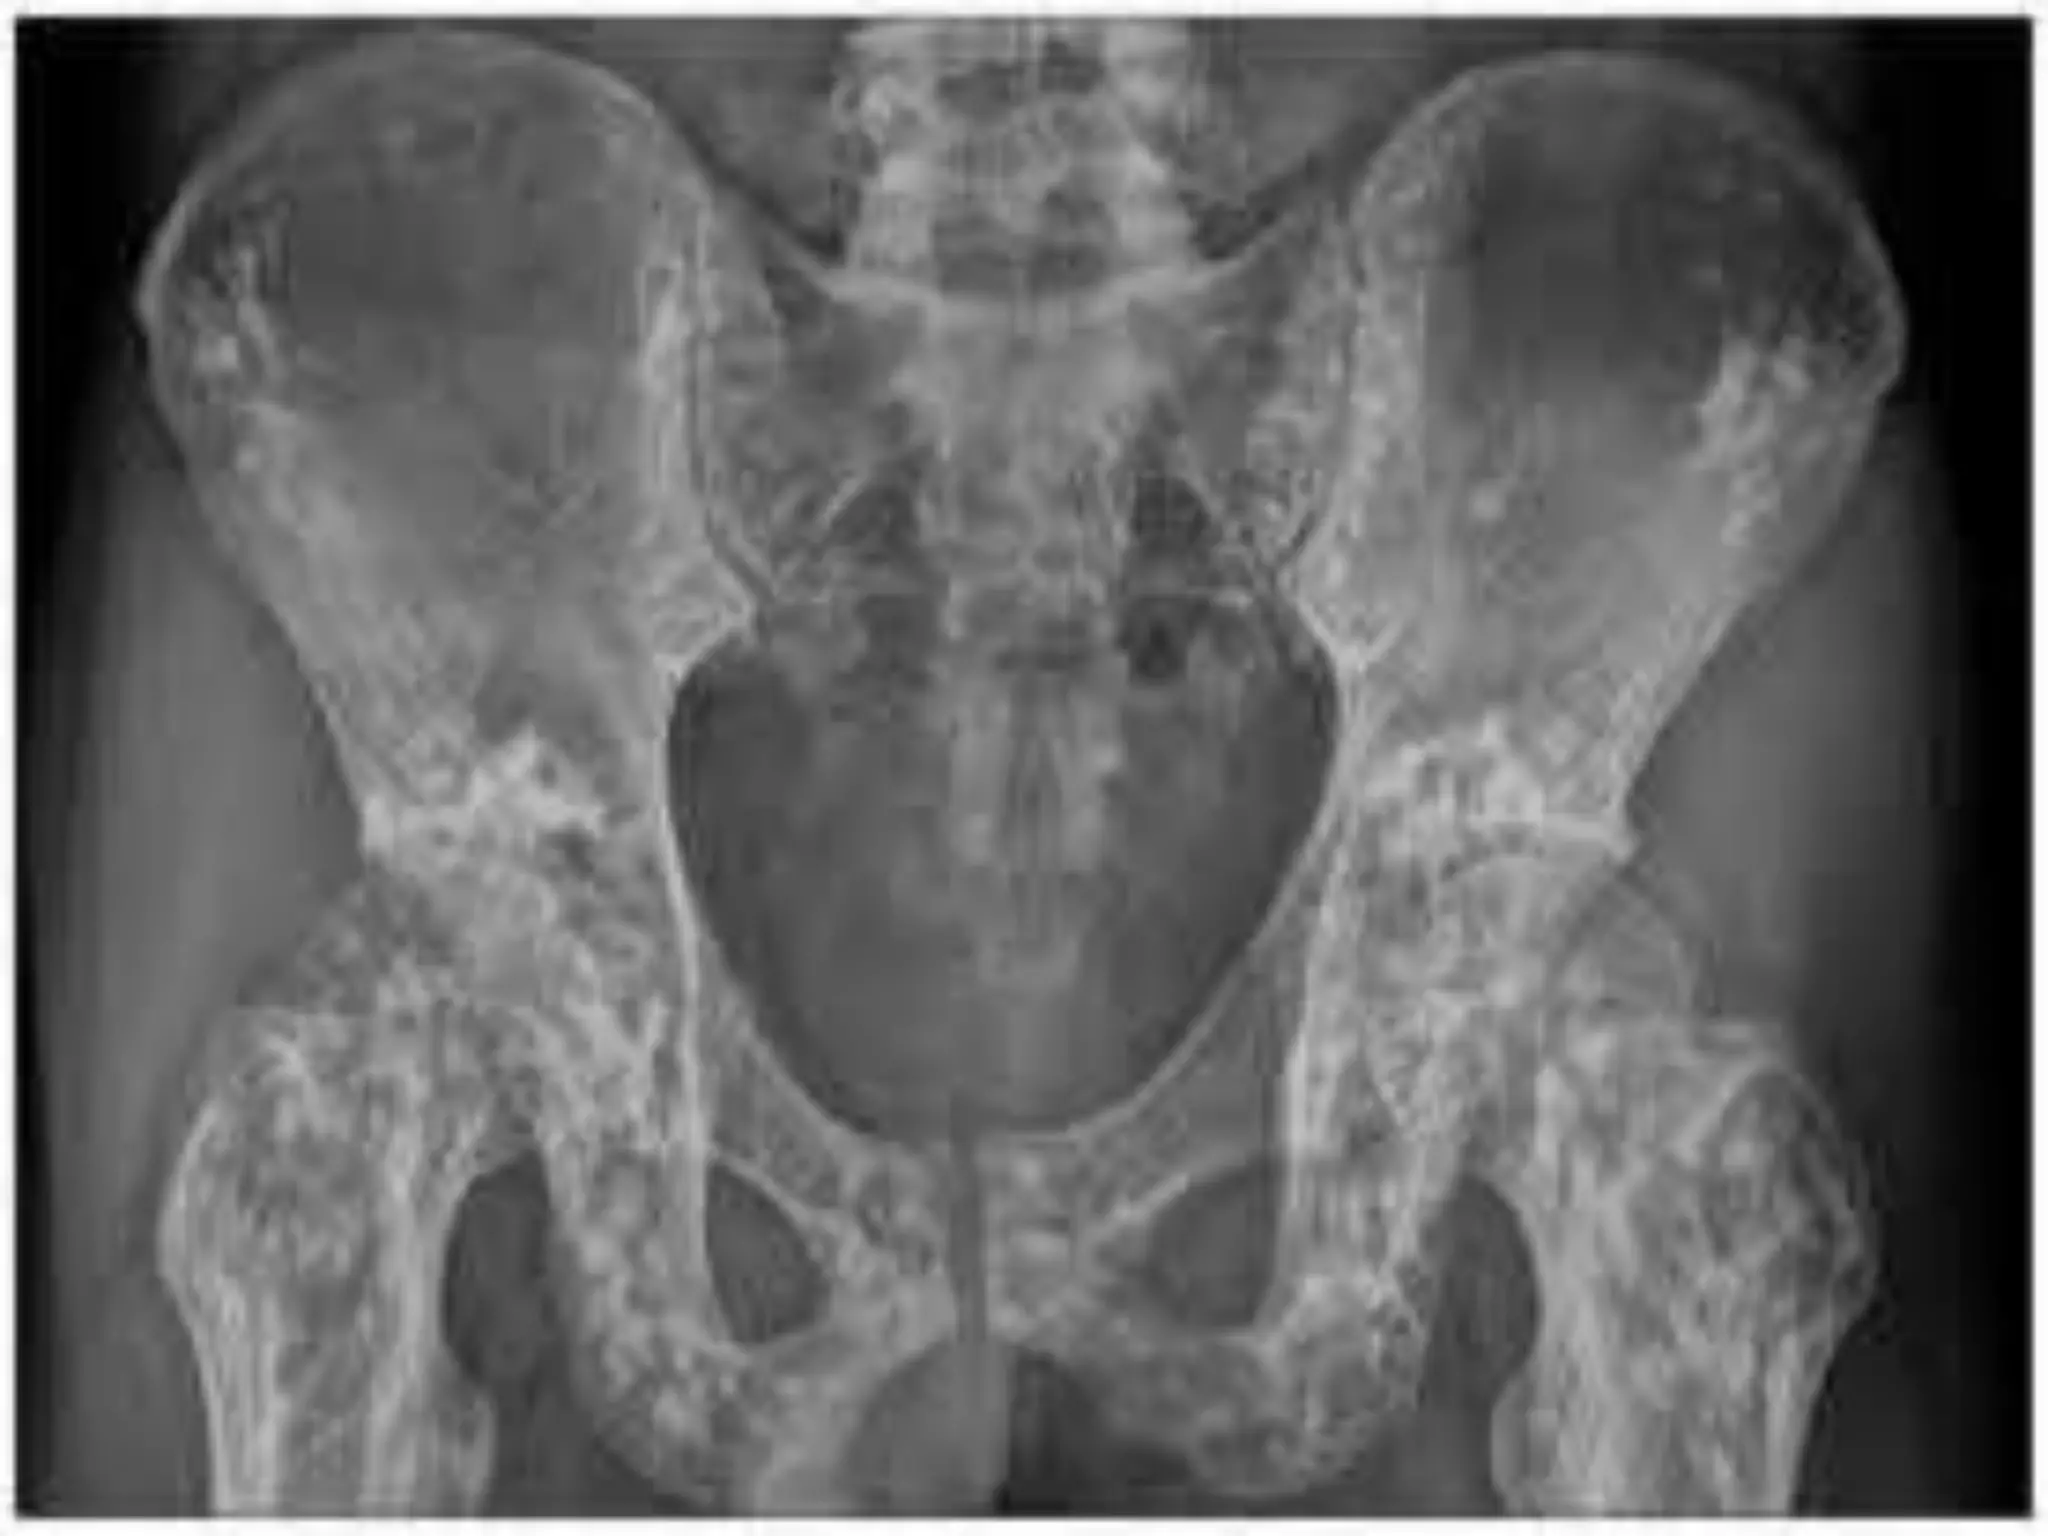

OSTEOPETROSIS

(MARBLE BONES/ ALBERS SCHONBERG DISEASE)

• Thickening & increased density of bones

• Two types

• a) osteopetrosis tarda

seldom symptoms,

discovered in adulthood(after fracture/x-ray),

vertebral end plates sclerosed & shows

stripped appearance (Rugger- Jersey Spine)

• b) osteopetrosis congenita

rare (autosomal recessive)

pancytopenia, haemolysis, anaemia,

hepatosplenomegaly,

optic nerve palsy/facial nerve palsy,

Repeated haemorrhage leads to death